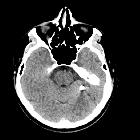

As is the case with low-velocity penetrating brain injuries, CT and CT angiography are the cornerstones of emergent imaging of all patients with penetrating injuries. Plain films have largely been replaced by CT and MRI is usually not indicated until later in the admission if at all. Of particular importance is the possibility that the penetrating material is ferromagnetic precluding safe MRI.

A number of features need to be assessed in patients with penetrating injuries, with care taken to carefully document findings as often these scans will be used in medicolegal proceedings.

Skull

The entry and exit wounds can be identified paying attention to the bone “beveling”. An inward beveling of the inner skull table is supportive of the entry wound, whereas the outward beveling of outer skull table suggests the exit wound. Often there is not an exit wound, especially in incomplete metal jacket bullets (e.g. hollow-point tip) that are designed to fragment and lose kinetic energy along their path .

Parenchyma and hematomas

The direction of tract(s) and the key structures they traverse along with the amount of hemorrhage, particularly if there are sizable hematomas that need evacuation. This is particularly the case for extra-axial hemorrhages that may occur due to vascular injury.

CT angiography

Angiographic imaging is used when there is evidence or suspicion of intracranial vascular injury. Projectiles or penetrating injuries that have traversed the base of skull or orbits have a high incidence of vascular injury .